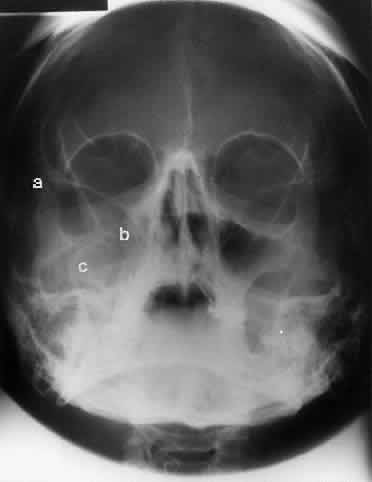

CALDWELL PROJECTION

In 1918 the evaluation of the frontal and ethmoid sinuses prompted Caldwell9 to describe a projection (Fig. 3) that eliminates the superimposition of the sphenoid bone on these paranasal sinuses. The patient is positioned with both the nose and forehead against the x-ray cassette while the x-ray beam is directed downward 15 degrees to 23 degrees to the canthomeatal line.5,6,9 This orientation also projects the petrous bones inferior to the orbit, thus avoiding obscuration of the orbital structures. As in the Waters view, the Caldwell view is a posterior-anterior projection. This excellent view of the frontal and ethmoid sinuses also allows good visualization of the orbital rims, greater and lesser sphenoid wings, lacrimal gland fossa, medial orbital wall, and both the superior and inferior orbital fissures.10 The innominate line is prominent in this view and represents the depression on the temporal surface of the greater wing of the sphenoid bone where it forms the medial wall of the temporal fossa or lateral wall of the orbit. This innominate line can be straight, end with a medial right angle turn, or continue inferiorly to form the outline of the pterygoid plate.8 A lack of continuity of the innominate line suggests a fracture of the lateral orbital wall.

Fig. 3. A. Schematic showing positioning for a Caldwell projection. (CM, canthomeatal line; CR, central ray) B. Radiograph of a Caldwell projection. The petrous ridge is positioned at the orbital floor. Detail of the orbital floor and maxillary sinus is blocked. C. The radiograph is taken at a steeper angle so the petrous ridge is now positioned lower within the maxillary antrum. (a, frontal sinus; b, innominate line; c, inferior orbital rim; d, posterior orbital floor; e, superior orbital fissure; f, greater wing of sphenoid;g, ethmoid sinus; h, medial orbital wall; i, petrous ridge; j, zygomatic-frontal suture; k, foramen rotundum) (A; Rao VM, Gonzalez CF: Plain film radiography and polytomography of the orbit. In Gonzalez CF, Becker MH, Flanagan JC [eds]: Diagnostic Imaging in Ophthalmology, pp 1–7. New York, Springer Verlag, 1986)